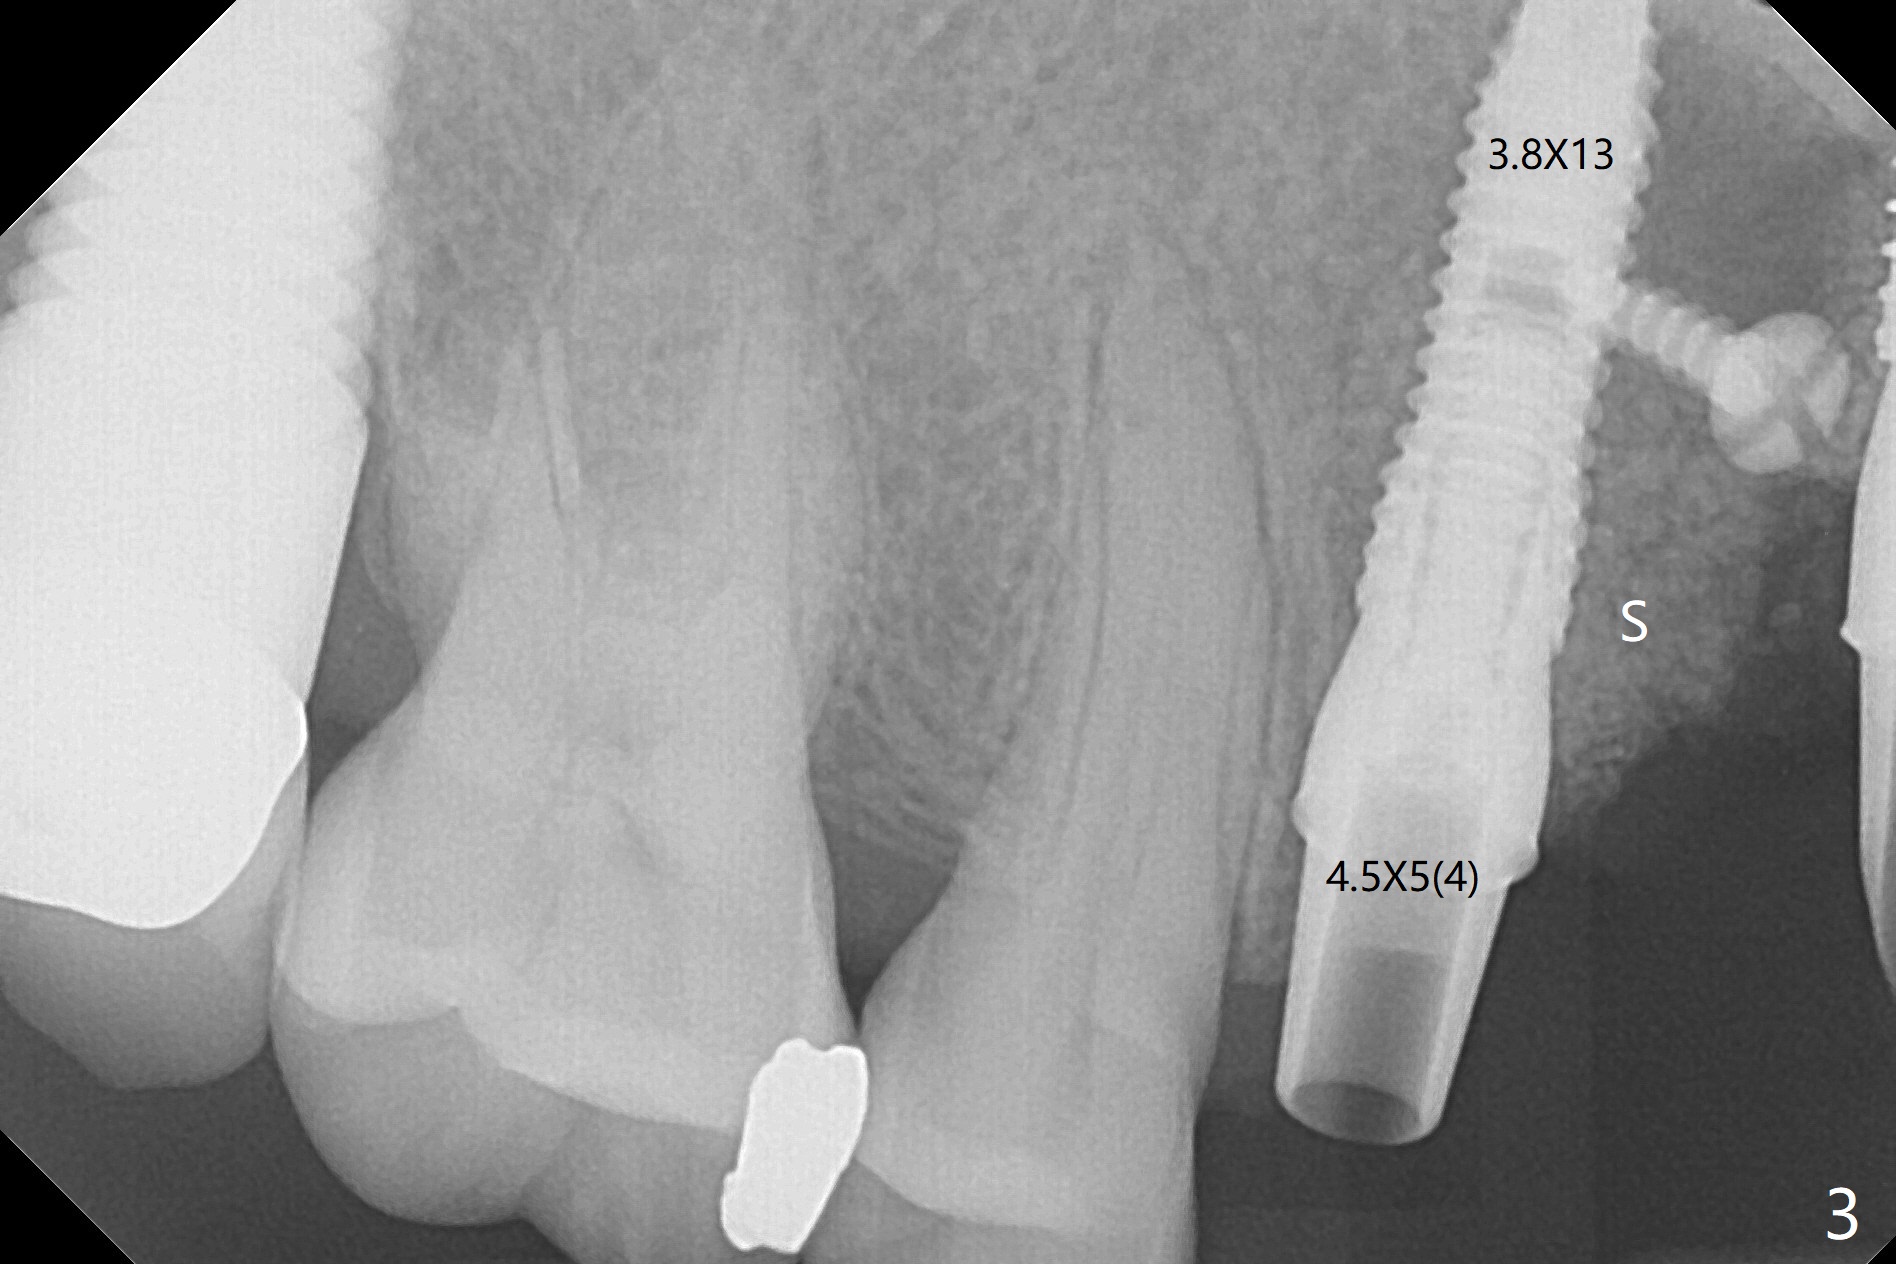

这个病例材料送到实验室作导板,实验员实在为难,只好徒手做。五号牙拔除证实颊侧骨板完全丧失,应该做位点保留(图一),但是病人非常恐惧,颊舌侧向牙槽窝好像很宽,开始尽量在舌侧建立钻洞,好像舌侧骨板太薄,又在稍微颊侧钻洞(图二),使用简易suction down stent控制钻洞方位。钻头大时,颊侧根尖有震动感觉,当时不明白为什么,稀里糊涂的植入3.8乘13毫米植体,扭力低,唯一欣慰的是颊侧放置PRF膜和粘性骨似乎到位(到根尖;图三:S),放置基台时,下面植体一起旋转,木已成舟,再次在基台周围放置骨粉。